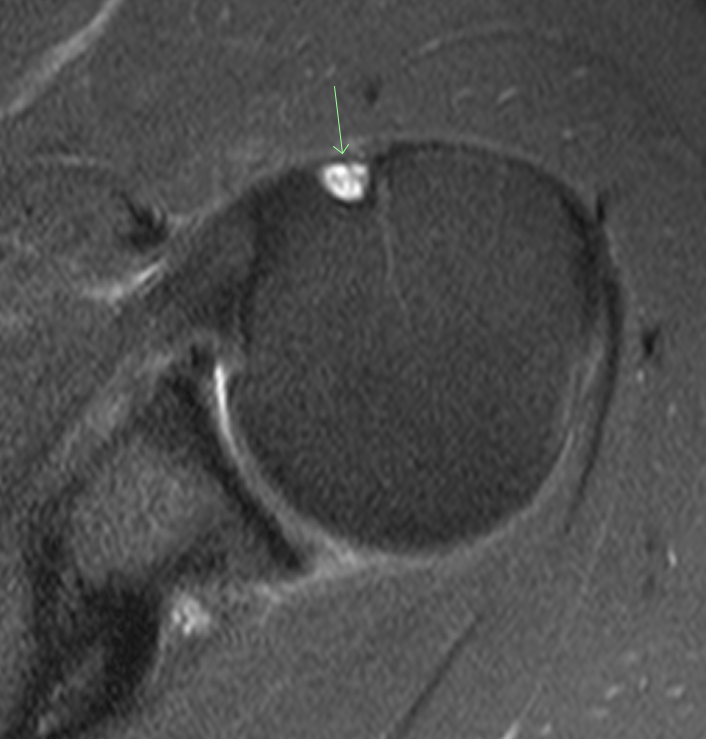

#CaseOfTheWeek‼️🥳‼️ ☢️🩻☠️Case#22☠️🩻☢️ #Mass 📲➡️➡️#Diagnosis❔❓❔ #FOAMRad #RadEd #MedEd #OrthoEd #OrthoTwitter @ssr_rwg @UWRadRes @ISSVA_org